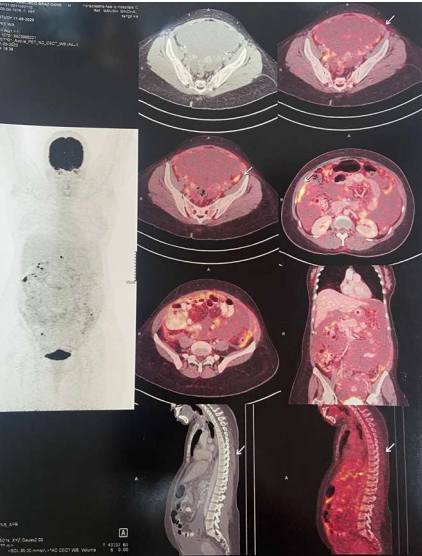

Mrs. S, 46 years, African descent, came with complaints of abdominal distension for four months and elevated serum immunoglobulin (alpha-1 and gamma globulins raised with M-spike of 1.16g/dL). She had a history of therapeutic ascitic tapping done thrice in Mozambique. There were no constitutional symptoms of fever, weight loss or night sweats. Detailed evaluation and workup for suspected malignancy after presentation to our hospital revealed bulky ovaries with cystic lesions in the ovary, gross ascites, omental thickening and thickening of peritoneal reflections on PET-CT scan. (Fig 1)

Fig 1: PET-CT showing FDG-avid omental & peritoneal thickening

Peritoneal tuberculosis is a form of extra-pulmonary tuberculosis, which may be insidious in onset with non-specific symptoms. The common symptoms are abdominal pain, distention and constitutional symptoms like fever, night sweats and weight loss. Incidentally, these are also the symptoms of ovarian cancer. In both these conditions, ascites is of the exudative type. Imaging may show the presence of peritoneal carcinomatosis type picture, as in the present case. PET-CT is also not able to distinguish the avidity as being due to cancer or tuberculosis1. To clinch the microbiological diagnosis, either ZN staining of the ascitic fluid or culture for AFB should be positive. However, being pauci-bacillary in nature, this may not always be possible. A large volume of ascites needs to be centrifuged and cultured to have acceptable sensitivity for detection2. ADA is sensitive for peritoneal tuberculosis, and tends to be higher in TB than in malignancy. Absolute cut-offs have not been defined, but levels higher than 30 U/L have been shown in some studies to be sensitive for tuberculosis3. In the present case, ADA was raised, but no other features were supportive, so peritoneoscopy and biopsy, which is the gold standard to diagnose both cancer and tuberculosis was carried out.